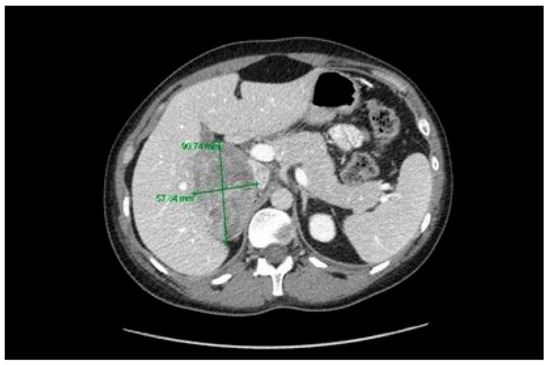

| Adrenocortical Carcinoma | Splice site 840—2A>T | P191fs*18 | |||||